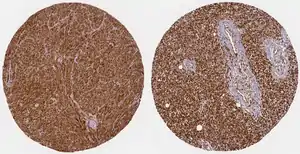

Cancers

WWTR1 (TAZ) is implicated a wide variety of cancers including melanoma, head and neck squamous cell carcinoma, breast cancer, non-small cell lung cancer, and others due to its high gene and histological expression, as well as correlation with increased metastasis and poorer survival in animal studies and patient data.[9] Along with the structurally similar co-regulator YAP, many studies have described their role in promoting oncogenesis, altering neoplastic metabolism, and generating resistance to therapeutic intervention.[8][9][32][33] In particular, TAZ overexpression conferred resistance to cisplatin chemotherapy as well as immunotherapy treatment with a PD-1 antibody.[32]